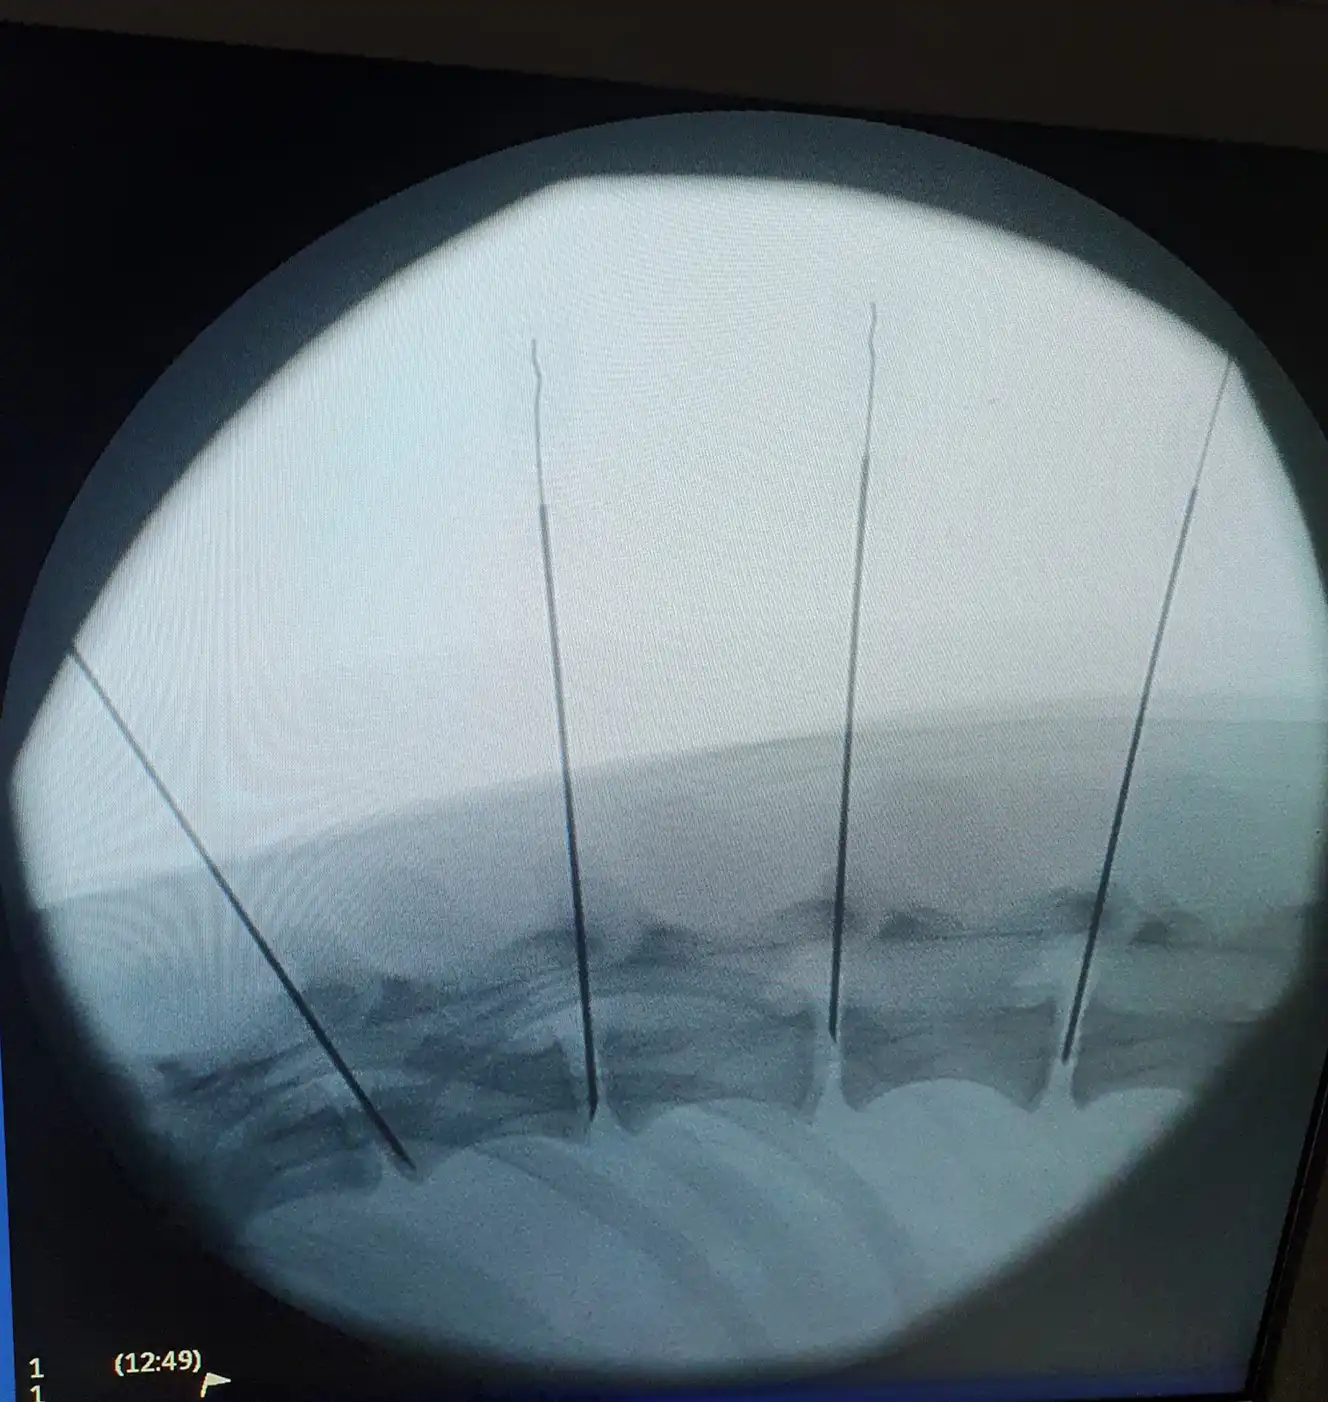

The treatment, known as the percutaneous intra-discal chondroitinase injection, delivers an enzyme directly to damaged intervertebral discs to dissolve the central part of the spinal disc and relieve pressure on the spinal cord.